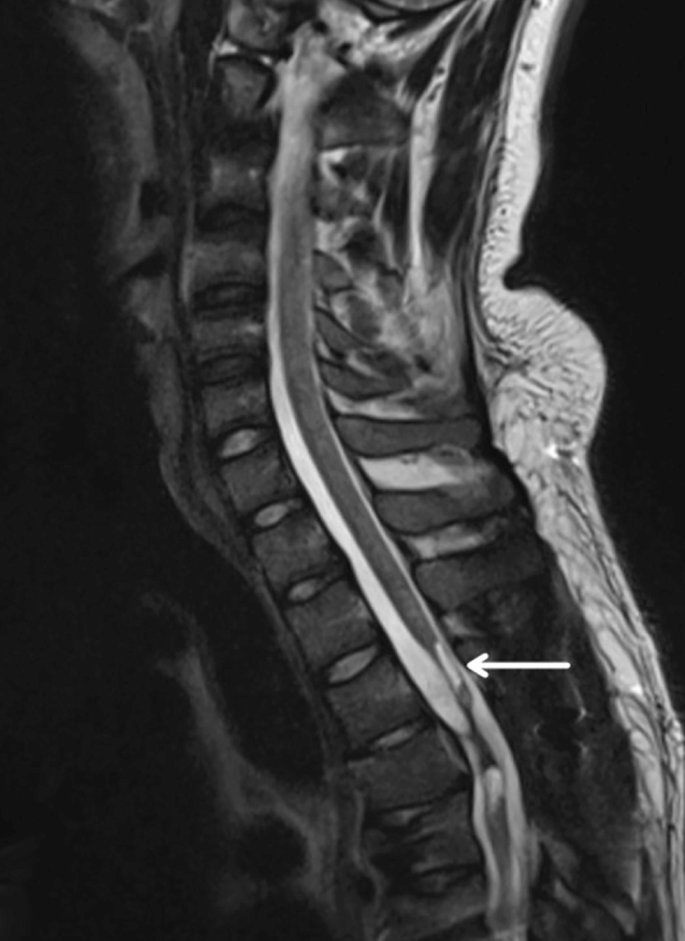

創(chuàng)傷性脊髓損傷是由于脊柱受到突然的強(qiáng)力撞擊,導(dǎo)致椎骨骨折、脫臼、擠壓或壓縮(圖1)。主要原因包括機(jī)動(dòng)車(chē)事故,其中汽車(chē)和摩托車(chē)碰撞占每年新增脊髓損傷病例的近一半。跌倒,尤其是65歲及以上人群的跌倒,是造成脊髓損傷的重要原因,約占60%。體育活動(dòng),例如沖擊性運(yùn)動(dòng)和淺水潛水,約占此類(lèi)損傷的10%。

圖1:X射線(xiàn)圖像顯示脊髓損傷,椎骨骨折和移位,如白色箭頭所示